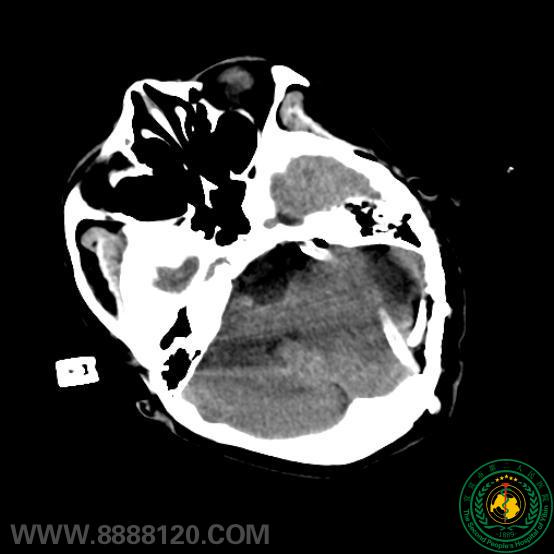

苦战7小时,宜宾市第二人民医院神外一科顺利成功切除后颅窝巨大肿瘤

苦战7小时,宜宾市第二人民医院神外一科顺利成功切除后颅窝巨大肿瘤40192